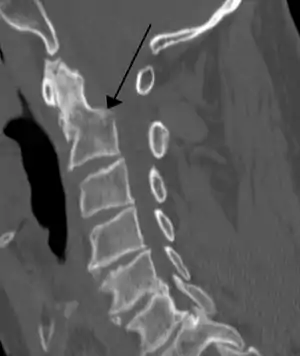

| A fracture of the base of the dens (a part of C2) as seen on CT. | |